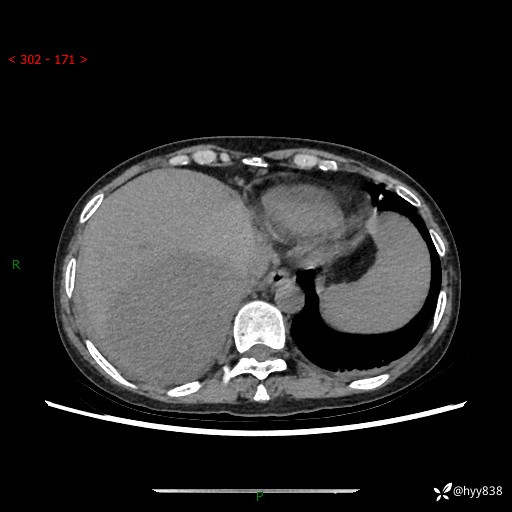

上腹部CT平扫